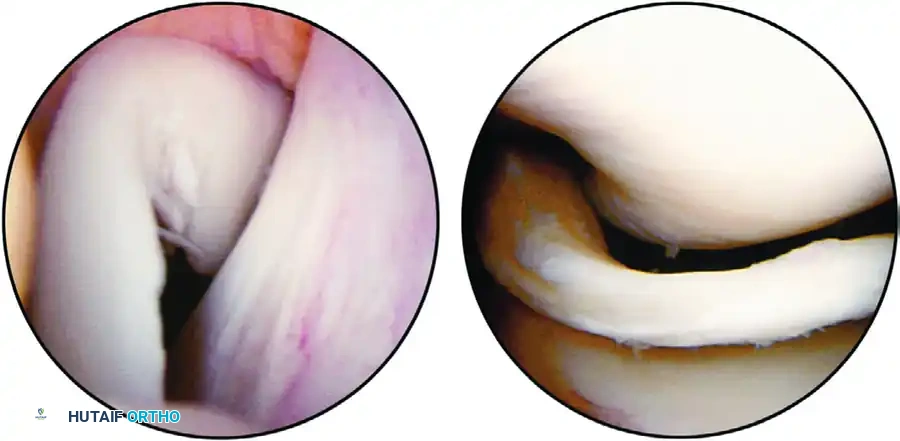

THE SYSTEMATIC SEVEN-COMPARTMENT EXAMINATION

To ensure no pathology is missed, the knee must be routinely divided into seven distinct compartments. The arthroscope should be swept through these regions systematically.

- Suprapatellar Pouch and Patellofemoral Joint: The examination begins superiorly. The undersurface of the articularis genu, the synovial lining, and the patellofemoral tracking are evaluated. The scope is swept medially and laterally to assess the patellar facets and the trochlear groove.

- Medial Gutter: The scope is directed down the medial side of the joint to inspect for loose bodies and assess the medial plica.

- Medial Compartment: A valgus stress is applied. The medial meniscus, medial femoral condyle, and medial tibial plateau are thoroughly inspected. The meniscus must be probed to assess for hidden inferior surface tears.

- Intercondylar Notch: The scope is moved centrally to evaluate the anterior cruciate ligament (ACL), the posterior cruciate ligament (PCL), and the ligament of Humphry or Wrisberg. The synovial covering of the PCL is often noted here.

- Posteromedial Compartment: This can be visualized by passing the arthroscope posteriorly through the intercondylar notch (between the PCL and the medial femoral condyle) or via a separate accessory posteromedial portal if visualization is inadequate.

- Lateral Compartment: The knee is placed in the figure-four position with varus stress. The lateral meniscus, lateral femoral condyle, and lateral tibial plateau are examined.

- Lateral Gutter and Posterolateral Compartment: The scope is swept down the lateral gutter. The popliteal hiatus and the insertion of the popliteus tendon are visualized. If the posterolateral compartment is incompletely viewed from the anterior portal, a direct posterolateral portal must be established.

The menisci are vital fibrocartilaginous structures that provide load transmission, shock absorption, joint stability, and proprioception. Recognizing the specific pattern of a meniscal tear during diagnostic arthroscopy is the most critical step in planning subsequent resection or repair.